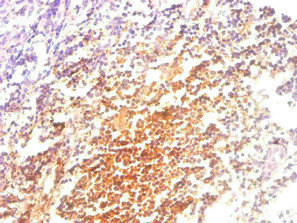

成熟MHC-I由重链、B2M与结合肽组成,B2M通过非共价相互作用稳定重链折叠并促进复合体转运至细胞表面;B2M缺失/下调会导致表面MHC-I表达丢失并削弱CD8+ T细胞识别,形成免疫逃逸的直接基础 [7,8]。抗原加工与呈递系统(APM)还依赖蛋白酶体亚单位(如PSMB8/9/10)产肽、TAP1/2转运以及ERAP修饰等环节,多个组分协同缺陷会显著降低新生肽-MHC-I复合体形成,并与免疫治疗抵抗相关 [8,9]。功能研究进一步支持因果性:双等位基因丧失或CRISPR敲除B2m可在体内产生对PD-1阻断的耐药表型,提示APM破坏在特定情境下足以驱动ICI失败 [7]。

大规模结直肠癌基因组研究显示,MSI-high肿瘤常出现抗原呈递机器的免疫编辑特征,包括B2M与HLA基因的双等位基因丧失(含拷贝数改变与拷贝中性LOH)[18]。临床队列进一步报告MSI-H CRC中B2M突变率可达约24%,且突变与蛋白表达缺失高度一致,支持“基因型—表型”的紧密关联 [19];同时,B2M热点突变在微卫星不稳定CRC中富集,且可能在免疫治疗前已存在,提示其既可能是早期演化事件,也可能在治疗压力下被选择 [20]。

在其他肿瘤中,B2M改变与HLA表达降低、CD8+ T细胞浸润减少等表型共同出现,强化了“抗原呈递受损→免疫逃逸”的解释框架,例如EBV阳性DLBCL中B2M突变与HLA表达降低及CD8+浸润减少并存 [21],并与多类EBV相关或血液肿瘤中HLA相关基因频繁受损的模式一致 [22]。在恶性胶质瘤中,针对HLA区域测序复杂性的研究亦识别出B2M与TAP基因体细胞突变,并提示其在复发GBM中可能富集,指向进展或治疗过程中选择压力的作用 [23]。在MSI/dMMR胰腺导管腺癌中,B2M失活可表现出原发与转移灶间异质性,提示治疗评估需关注空间差异与转移部位的重要性 [24]。

在DLBCL中,B2M等基因突变与多处结外侵及(ENI)、更差预后以及TME层面的Treg招募增强、基质基因表达降低相关;动物模型亦提示B2M突变与骨髓侵及相关,暗示其可能通过抗原呈递下降与免疫浸润谱改变共同驱动侵袭表型 [25]。但目前对其如何直接驱动Treg募集(如趋化网络或基质改造)仍以相关性为主。

在林奇综合征相关CRC中,即便存在肿瘤细胞B2M丧失,仍可观察到PD-L1上调与丰富的CD3+/CD8+浸润,提示B2M缺失并不必然等同于“完全免疫隐匿”,应结合更广泛免疫景观解释ICI敏感性 [26]。此外,PMBL整合基因组研究显示包括B2M在内的多种免疫逃逸相关基因频繁突变并与JAK-STAT、NF-κB改变共存,支持免疫回避为该亚型核心机制之一 [27];滤泡淋巴瘤单细胞研究亦在Treg细胞中识别出与免疫检查点共表达网络相关的基因集,包含B2M,提示其在免疫细胞内源性表达与调控中可能具有意义,但仍缺乏直接功能验证 [28]。